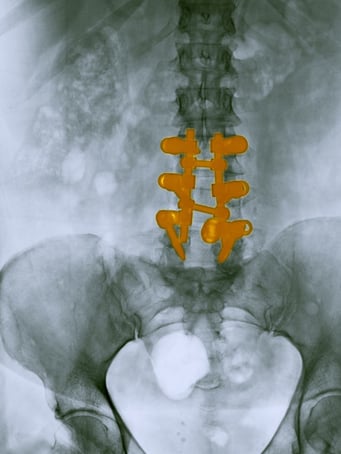

L’électrode sera implantée de manière percutanée (sous anesthésie locale, le patient éveillé) ou bien chirurgicalement (sous anesthésie générale) à la surface de la dure-mére.

Electrode per-cutanée visant à soulager des douleurs chroniques post-chirurgicales